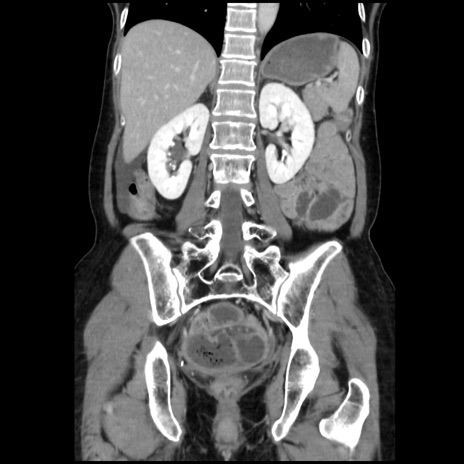

症例32(冠状断像)

【症例】40歳代 女性

【主訴】上腹部痛、嘔気・嘔吐

【現病歴】約9時間前頃から急に上腹部痛、嘔気、嘔吐が出現。改善しないため救急要請。

【既往歴】子宮頚癌(広汎子宮全摘術、放射線療法)、腸閉塞

【身体所見】腹部:平坦、軟、腸雑音亢進、上腹部を中心に腹部全体に圧痛あり。

【データ】WBC 8400、CRP 0.03